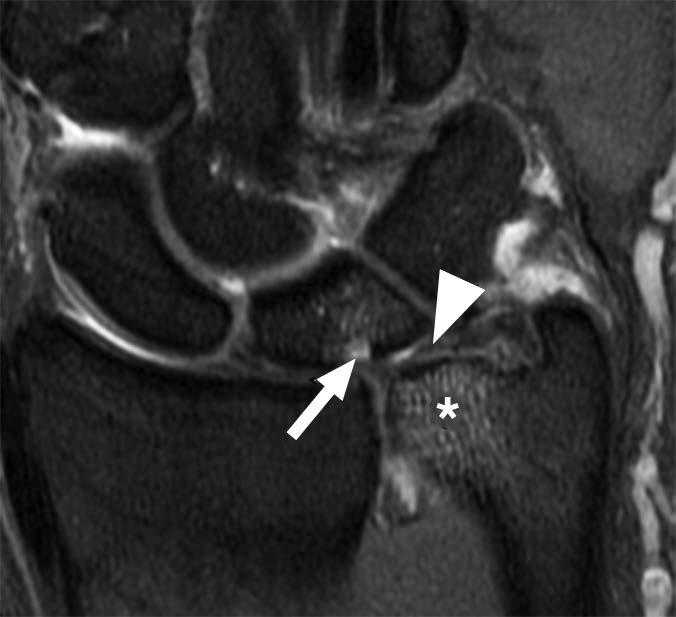

In comparison with acute traumatic injuries to the TFCC, which may affect various components of the complex, chronic ulnar abutment typically causes central degeneration and perforation of the triangular fibrocartilage disk proper, as outlined by the Palmer classification. The spectrum of progressive pathologic changes in ulnar abutment includes degenerative tearing of the TFCC, ulnar-sided chondromalacia, tears of the lunotriquetral ligament, and lunotriquetral instability—and, in advanced stages, osteoarthritis of the distal radioulnar joint and ulnar side of the radiocarpal compartment. The typical areas of cartilage loss and associated reactive marrow changes are localized to the ulnar head, ulnar side of the proximal aspect of the lunate, and radial side of the proximal aspect of the triquetrum (Fig. 1).

Radiography provides the most accurate determination of the ulnar variance and cannot be substituted with other imaging modalities, particularly in the detection of subtle changes that can be determined only by standard radiographic positioning. MRI provides detailed assessment of the TFCC, bone, and articular cartilage. MRI and CT arthrography can be used to determine the integrity of the TFCC and lunotriquetral ligament.